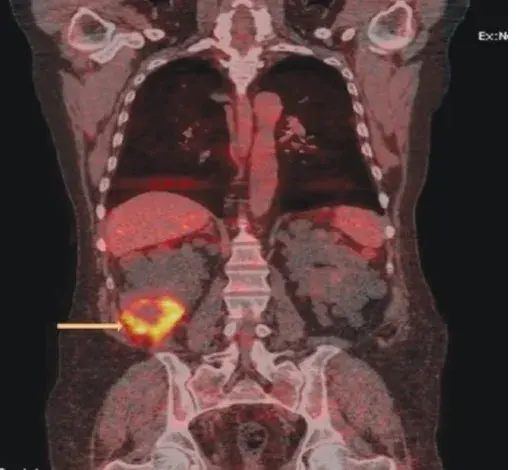

Os cálculos coraliformes são formados em sua maioria por cálculos de estruvita (fosfato amônio de magnésio) e possuem uma forte associação com infecção do trato urinário (ITU) causada por bactérias produtoras de urease. A formação desses cálculos é rápida, semanas a meses, e se não instituído tratamento adequado pode ocorrer invasão completa do sistema coletor